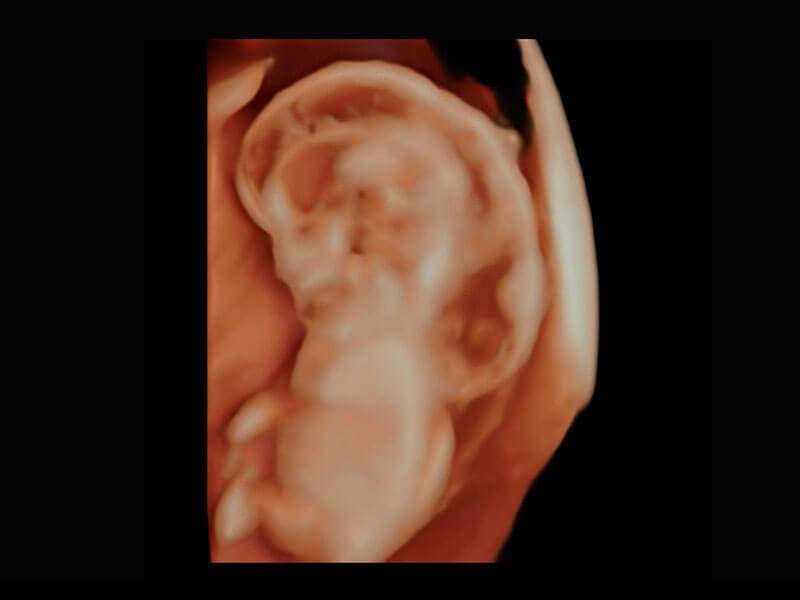

P60在胎儿早孕期超声筛查中为您带来优异的图像质量。

早孕-胎心

高分辨率容积成像-早孕胎儿